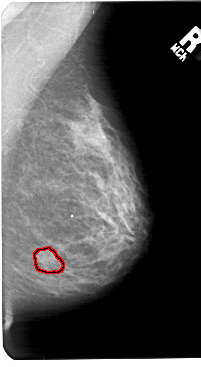

FILE: A_1569_1.RIGHT_MLO.OVERLAY

TOTAL_ABNORMALITIES 1

ABNORMALITY 1

LESION_TYPE MASS SHAPE IRREGULAR MARGINS ILL_DEFINED

ASSESSMENT 4

SUBTLETY 1

PATHOLOGY BENIGN

TOTAL_OUTLINES 1

BOUNDARY